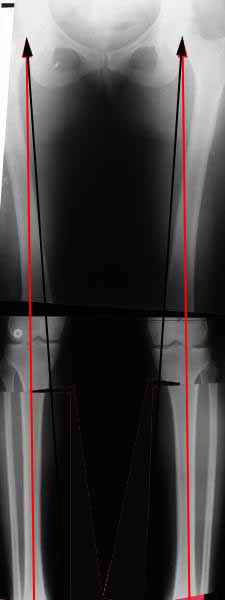

Александр, а не могли бы вы представить ваши схемы расчета? С учетом

осей?

AVM> Александр, а не могли бы вы представить ваши схемы расчета? С учетом

Вот, с учетом и без учета, и на разных уровнях...

AC> Вот, с учетом и без учета, и на разных уровнях...

AC> Саша Артемьев, может, для данного случая свой вариант нарисуешь?

Из приведнной схемы не совсеим понял что означают разноцветные линии.

И зачем латерализация периферического фрагмента. Я всегда делаю медиализацию. См схему. И для данного случая медиализация подходит как нельзя лучше.

a> Из приведнной схемы не совсеим понял что означают разноцветные линии.

Черные - это нынешняя механическая ось. Красные - это планируемая правильная ось.

a> И зачем латерализация периферического фрагмента.

;-) Читайте Палея. Стр. 114-115.

a> Я всегда делаю медиализацию. См схему. И для данного случая

Медиализация - это чисто эстетический прием, как я понимаю. Поскольку если делать остеотомию ниже вершины деформации, для восстановления оси надо делать смещение по ширине, в данном случае как раз латерализацию.

А вот на схемке без осей - там на разных уровнях (который правильнее?) устранение варуса чисто открытым клином без медиализации-латерализации. Если как-то так сделать - этого недостаточно будет?